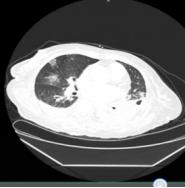

入院血常规提示白细胞计数及中性粒细胞绝对值升高,淋巴细胞绝对值偏低。胸部CT提示双肺感染,考虑病毒性肺炎可能,双侧胸腔积液,双肺下叶膨胀不全(图2-4-55)。

图2-4-55 2020年2月20日胸部CT